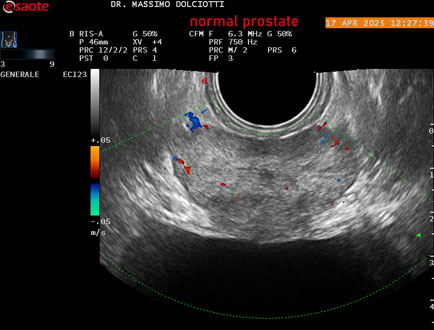

Data inserimento: 01/10/2025

Ecografia del: 17/04/2025

Strumento: Esaote MyLab Eight

Sonda: Convex Multifrequenza 1-8 MHz, Endocavitaria Multifrequenza 3-9 MHz e 3-13 MHz

Età Paziente: M 35 anni

Motivazione dell'esame: disuria.

Commento all'esame: le immagini ed il video documentano la prostata di ecostruttura regolare e morfovolumetria normale con diametro trasversale di 40 mm, diametro anteroposteriore di 21 mm e diametro longitudinale di 43 mm, con volume prostatico calcolato di 18 cc (v.n. < 20 cc), il profilo prostatico è regolare e netto, non si documentano calcificazioni intraghiandolari, la vascolarizzazione della ghiandola è normale. La vescicola seminale destra presenta diametro longitudinale di 44,4 x 7,8 mm, la vescicale seminale sinistra ha diametro longitudinale di 45,3 mm x 7,2 mm.

Conclusioni: prostata normale (normal prostate).